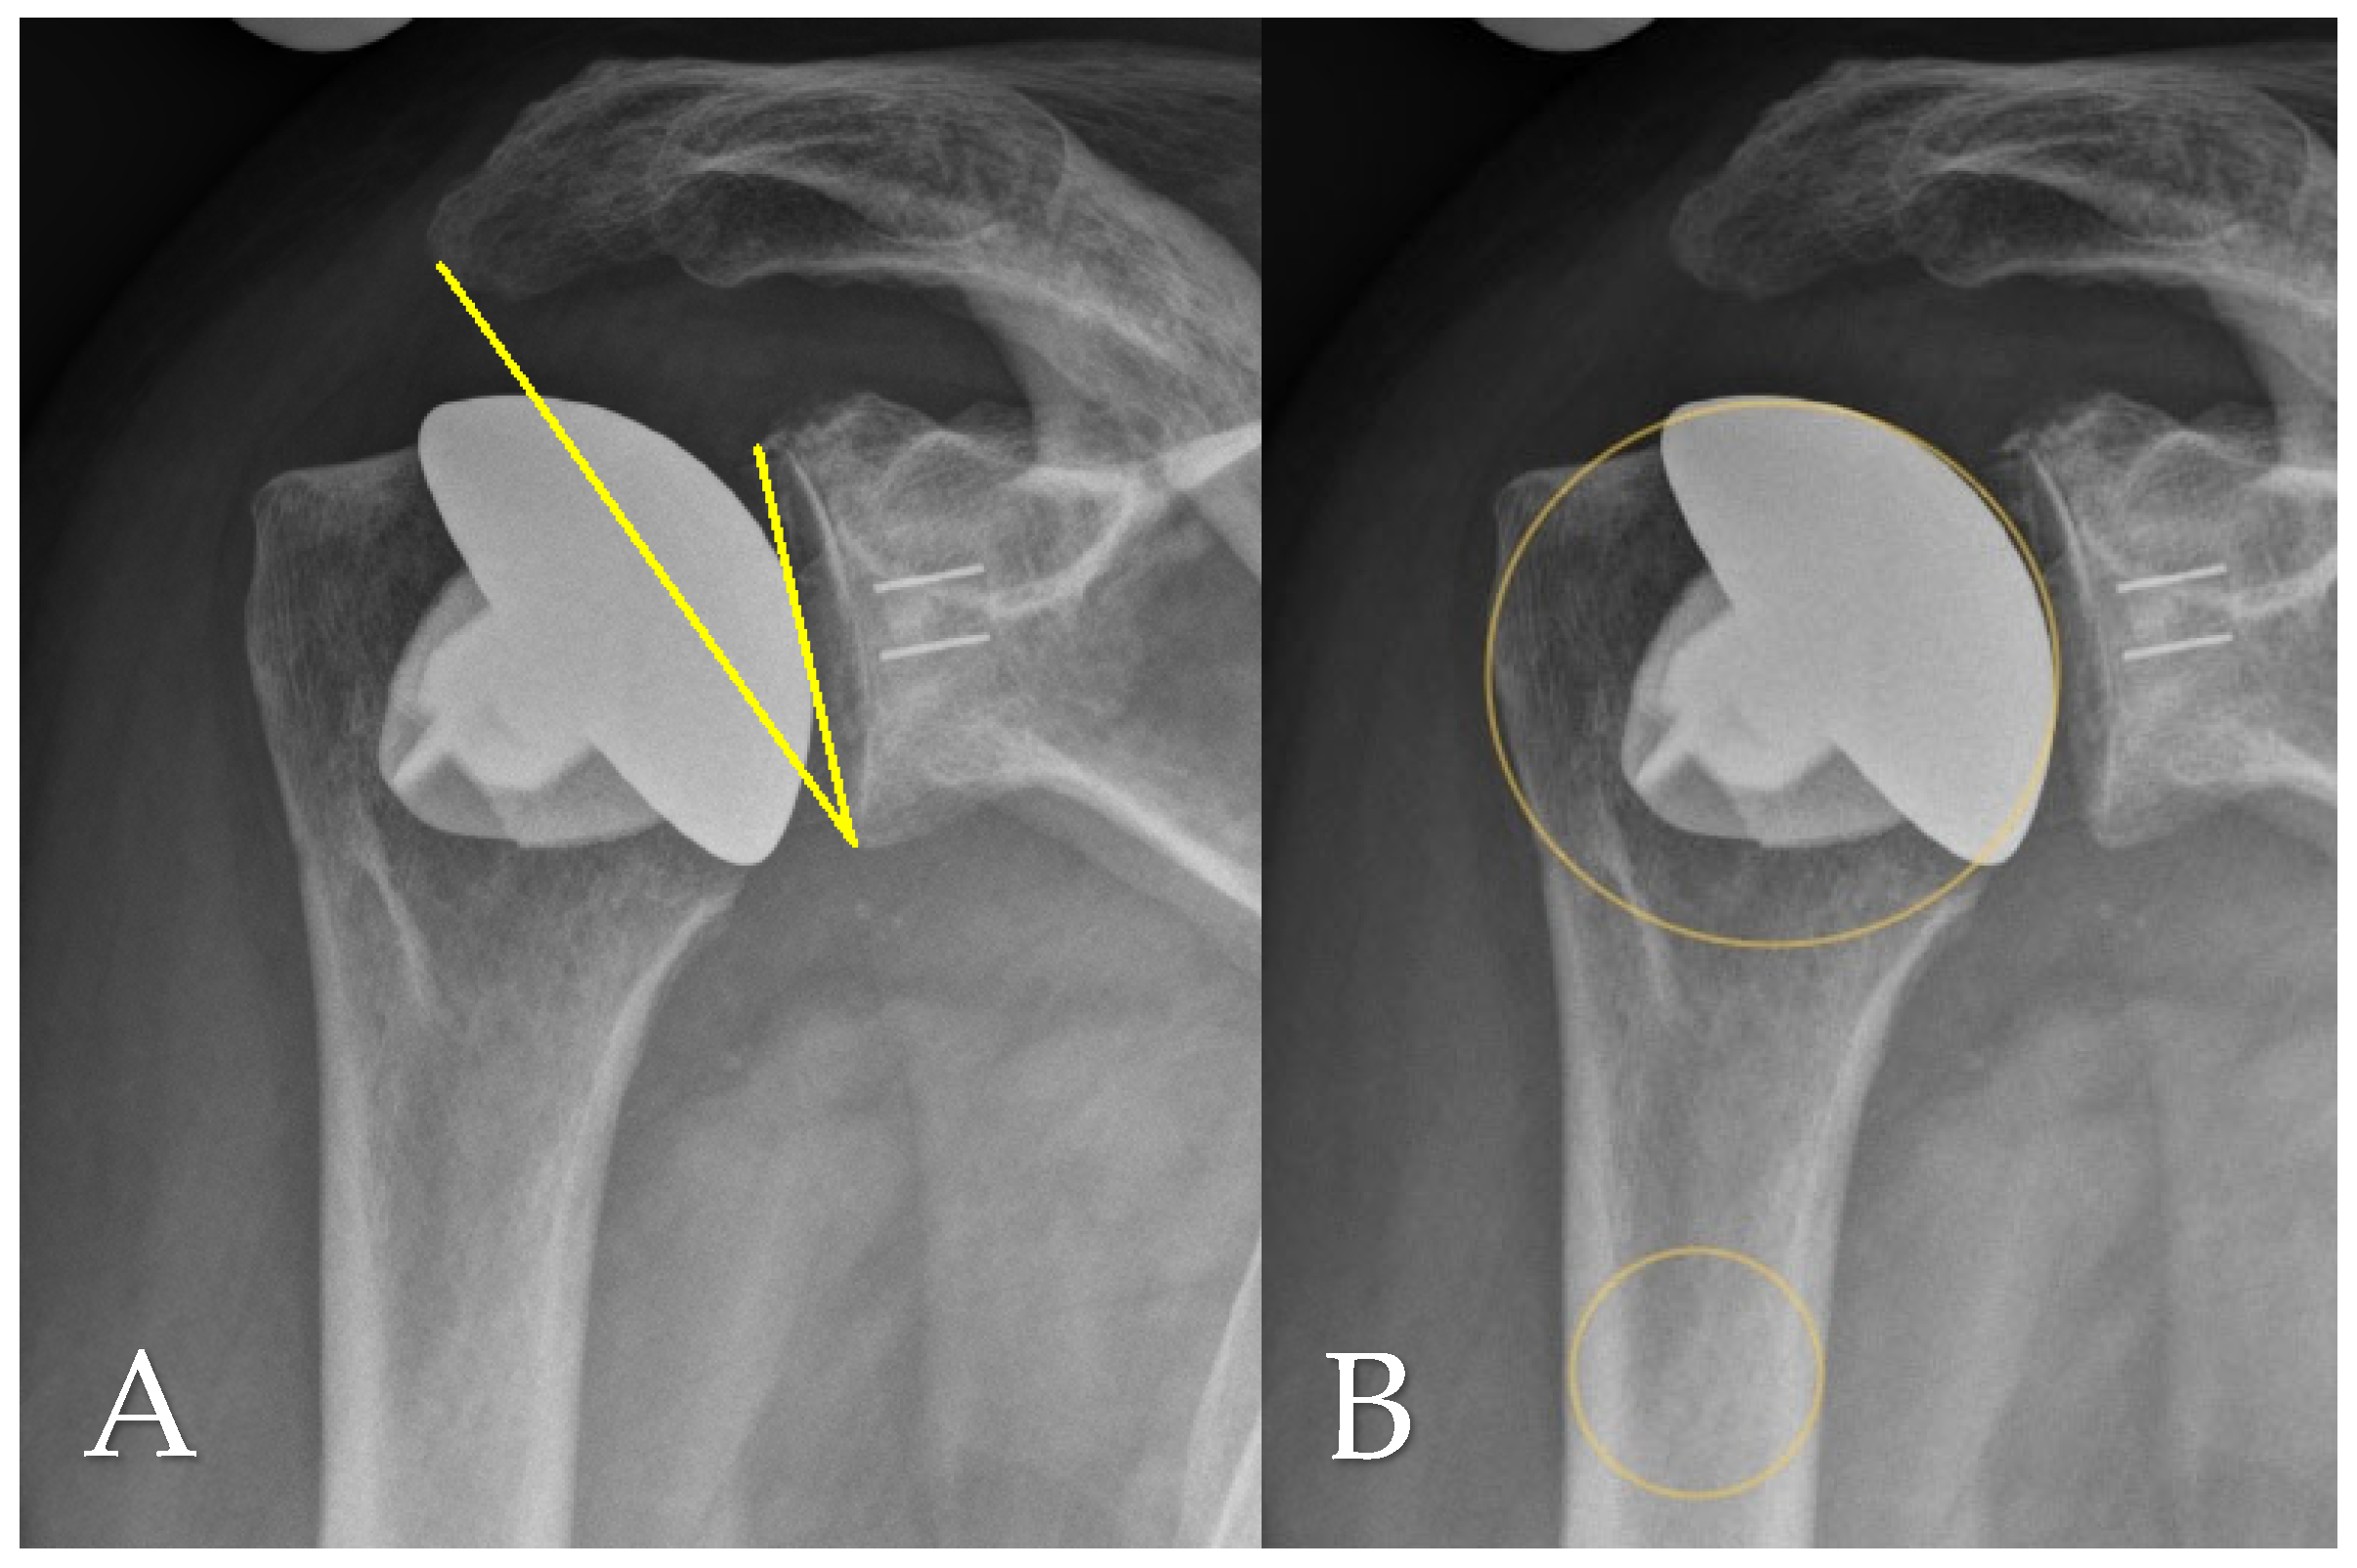

2.4. Radiographic Assessment